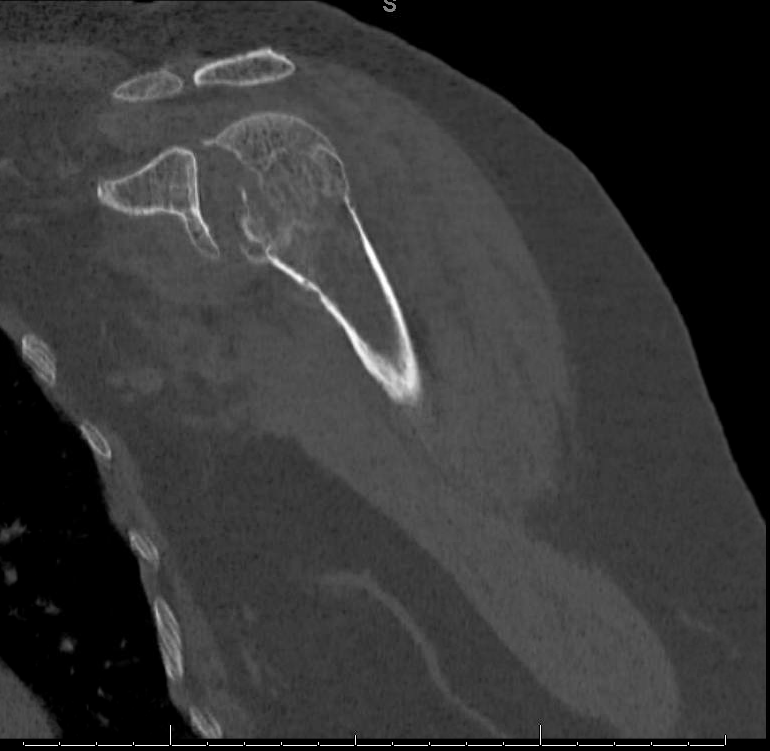

Displaced fracture of greater tuberosity of right humerus. Fracture of greater tuberosity of humerus.

Displaced isolated greater tuberosity fractures are rare injuries that require operative treatment to optimize rotator cuff function and prevent painful subacromial impingement. Header codes like s42.25 require more digits to indicate the appropriate level of specificity. It is important to differentiate these two entities, as their treatment is different (typically nonsurgical. A lack of consensus exists regarding ideal management of these injuries because of the paucity of literature on the subject. The greater tuberosity fragment detaches with its attached rotator cuff and will characteristically have a. This can make reducing fractures of the greater tuberosity difficult, which typically displace superiorly and posteriorly. S42.253d encounter for fracture with routine healing. S92 fracture of foot and toe, except ankle. This condition is a fracture of the bony bump that is located opposite of the head of the humerus. Displaced isolated greater tuberosity fractures are rare injuries that require operative treatment to optimize rotator cuff function and prevent painful subacromial impingement. Anteroinferior labral injury seen in axial and coronal. You have sustained a fracture of your greater tuberosity of your shoulder. Lateral fluoroscopy view of the proximal humerus with the greater tuberosity reduced after it was sutured to the plate. Greater tuberosity fracture, anterior fracture dislocation shoulder. Displaced fracture of greater tuberosity of unspecified humerus, subsequent. And an amount less than usd 10,000. Emergency room report tom pounds was transported to the er via ambulance following a motorcycle accident.